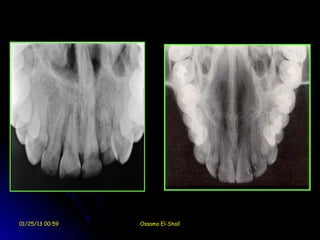

Occlusal films

Occlusal films are use to radiographically

clarify the anatomical structures and

the pathological conditions of the

maxilla or mandible in the bucco-lingual

dimension.

Occlusal films may use for the following

purposes:

1.     Obtaining gross views for the jaws in the

bucco-lingual dimension.

2.     Detection location and extent of fractures.

3.     Detection of the bucco-lingual direction of

impactions and supernumerary teeth.

4.     Detection of bucco-lingual direction of

displaced fracture.

5.     Detection of salivary gland or duct stone

especially in the mandible.

6.     Localization of foreign bodies such as

broken needle.

7.     Determination of the shape of dental

arches.

01/25/13 00:59        Ossama El-Shall